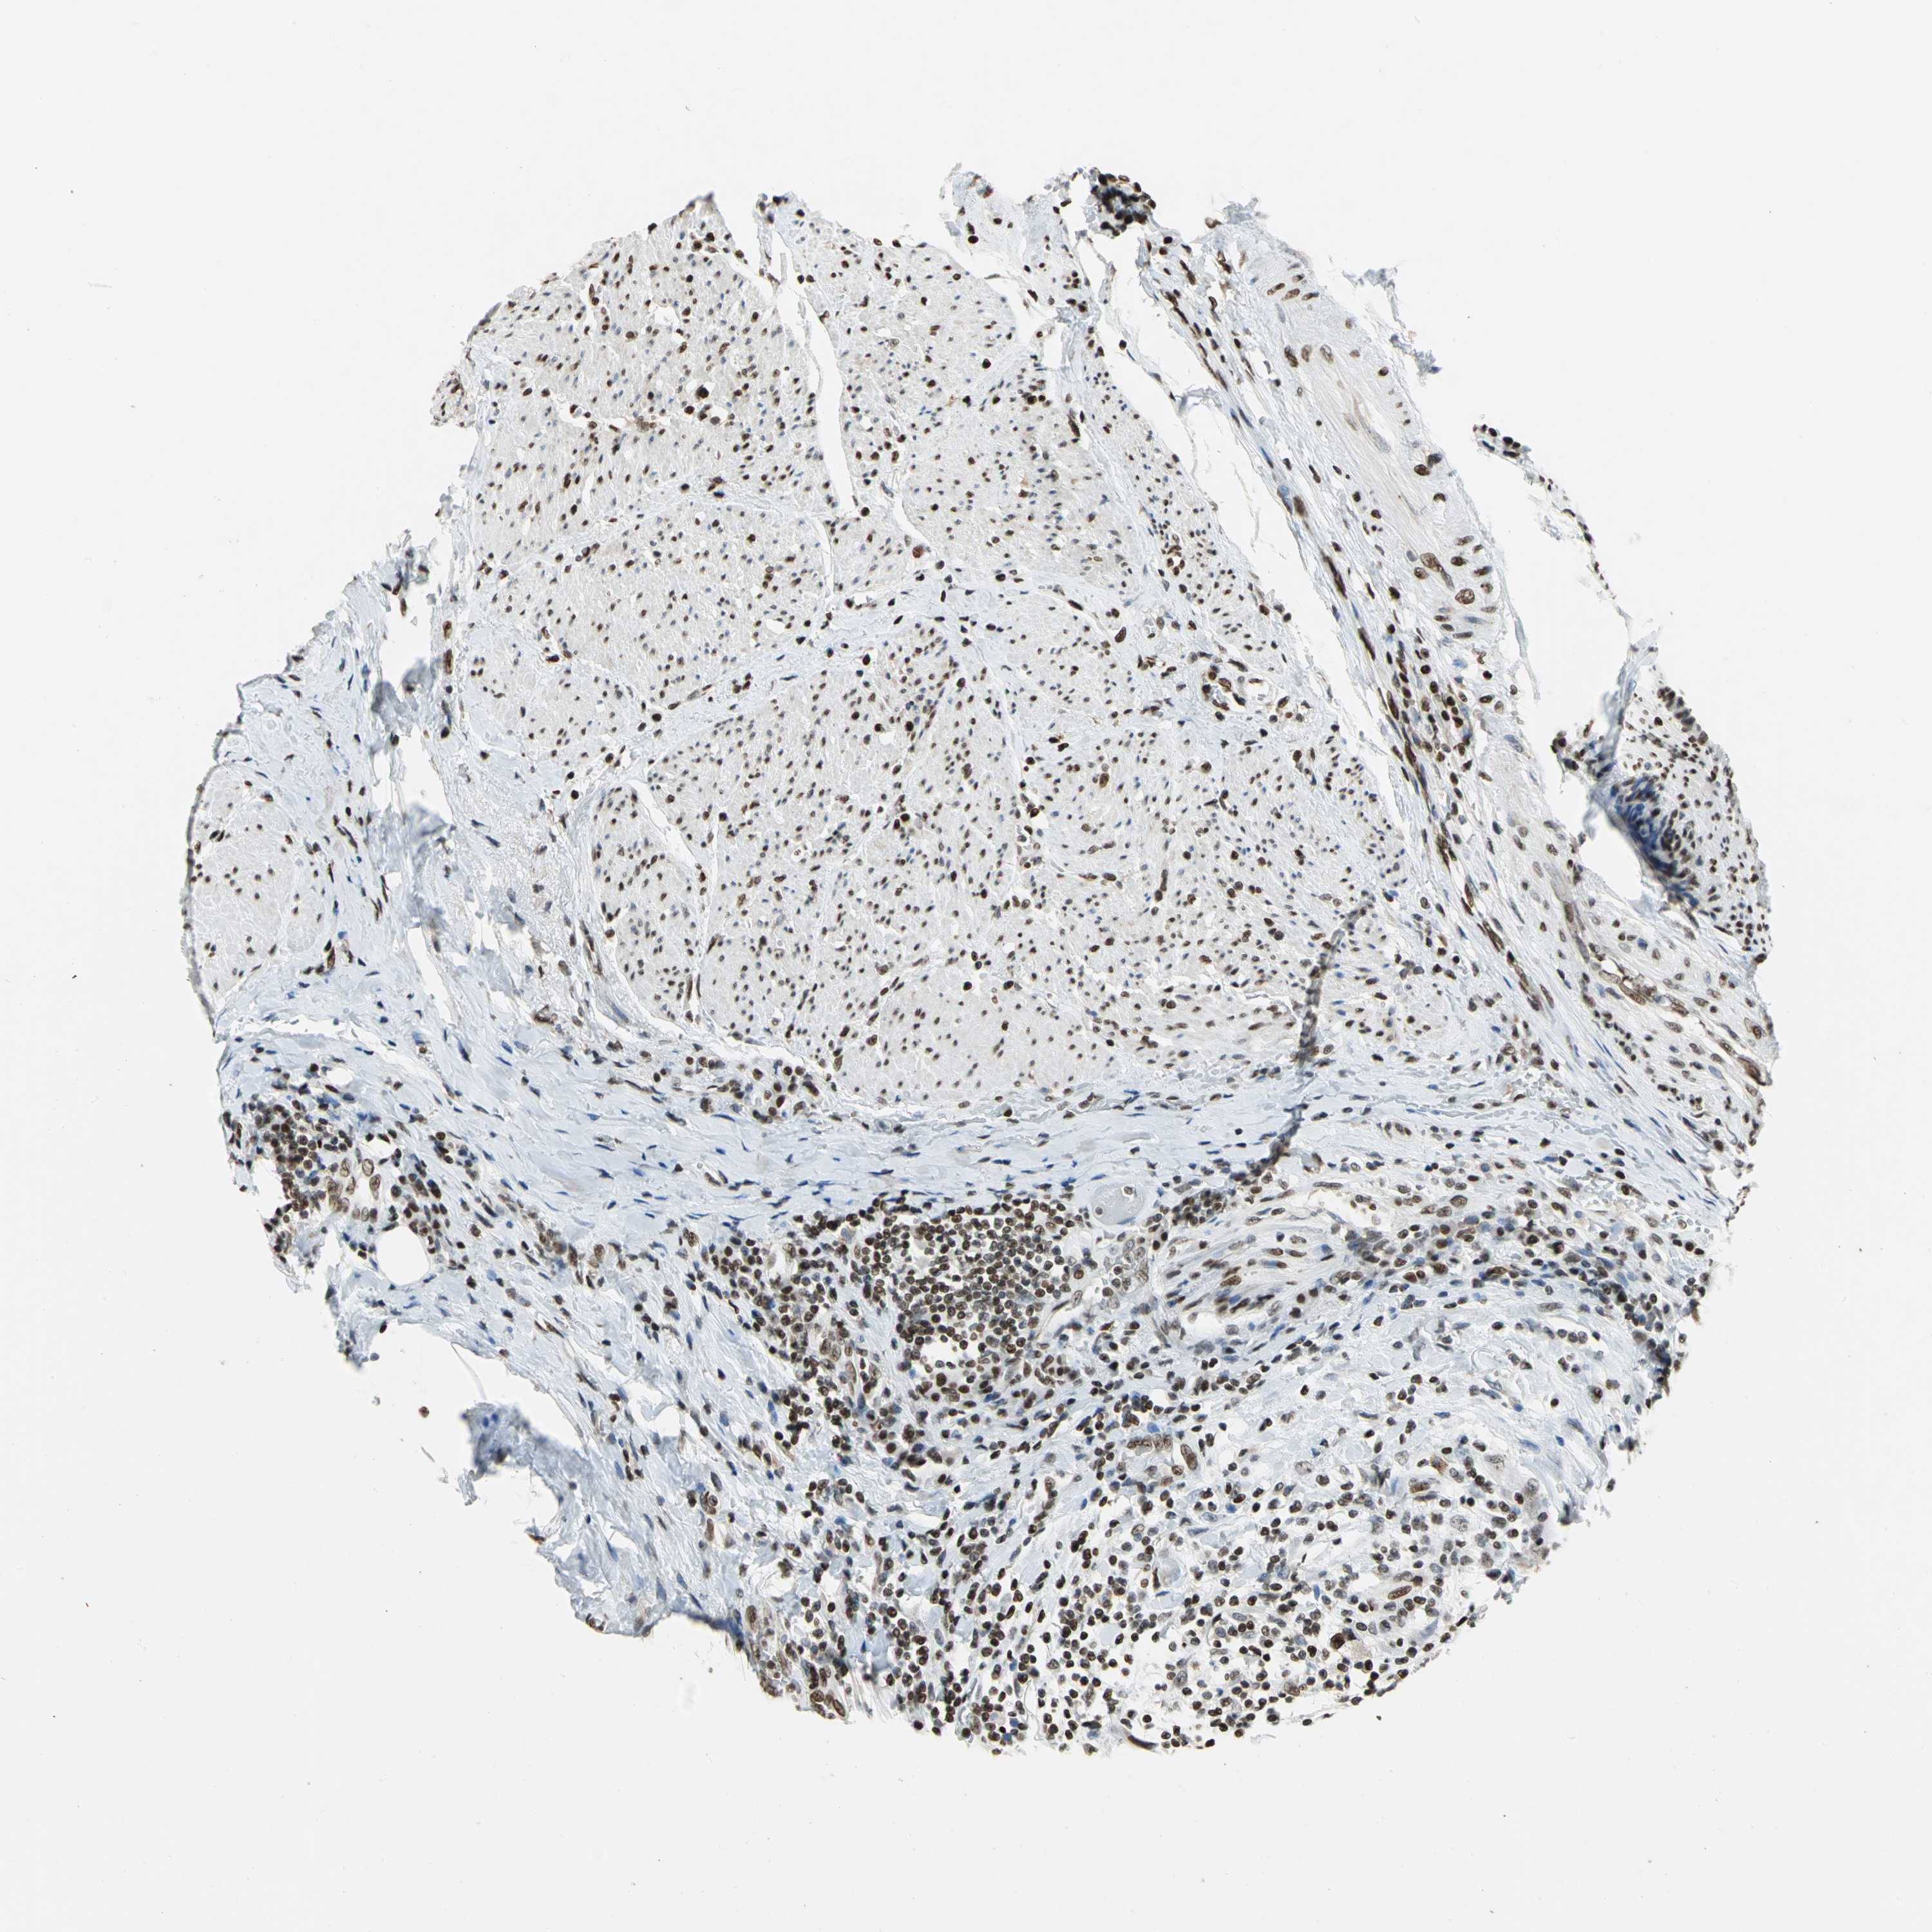

UROTHELIAL CANCER - Protein expressioni

A mouse-over function shows sample information and annotation data. Click on an image to view it in a full screen mode. Samples can be filtered based on level of antibody staining by selecting one or several of the following categories: high, medium, low and not detected. The assay and annotation is described here.

Note that samples used for immunohistochemistry by the Human Protein Atlas do not correspond to samples in the TCGA dataset.

Antibody stainingi

Antibody staining in the annotated cell types in the current human tissue is reported as not detected, low, medium, or high, based on conventional immunohistochemistry profiling in selected tissues. This score is based on the combination of the staining intensity and fraction of stained cells.

Each image is clickable and will lead to virtual microscopy that enables deeper exploration of all samples and also displays staining intensity scores, fraction scores and subcellular localization as well as patient and tissue information for each sample.

Antibody HPA003506

Antibody CAB005873

Staining

High

Medium

Low

Not detected

Intensity

Strong

Moderate

Weak

Negative

Quantity

>75%

75%-25%

<25%

None

Location

Nuclear

Cytoplasmic/membranous

Cytoplasmic/membranous,nuclear

Urothelial carcinoma, High grade

Urothelial carcinoma, Low grade